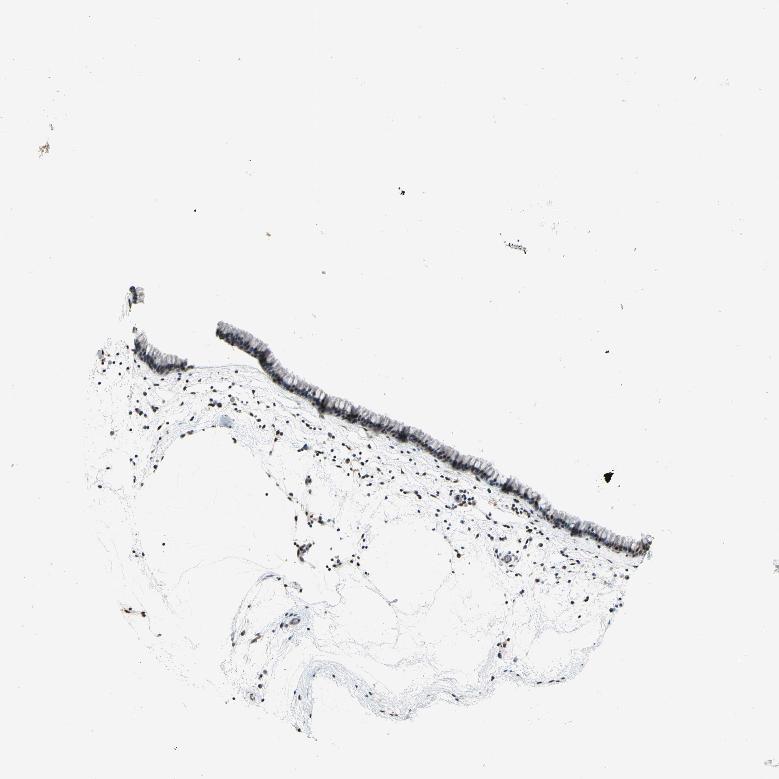

TISSUE PRIMARY DATA NASOPHARYNX Show tissue menu

Nasopharynx

NASOPHARYNX - Antibody stainingi

Antibody staining in the annotated cell types in the current human tissue is reported as not detected, low, medium, or high, based on conventional immunohistochemistry profiling in selected tissues. This score is based on the combination of the staining intensity and fraction of stained cells.

Each image is clickable and will lead to virtual microscopy that enables deeper exploration of all samples and also displays staining intensity scores, fraction scores and subcellular localization as well as patient and tissue information for each sample.

Antibody HPA031092Antibody HPA031093Antibody HPA031095Antibody CAB009315

Respiratory epithelial cells HighHighHighMedium